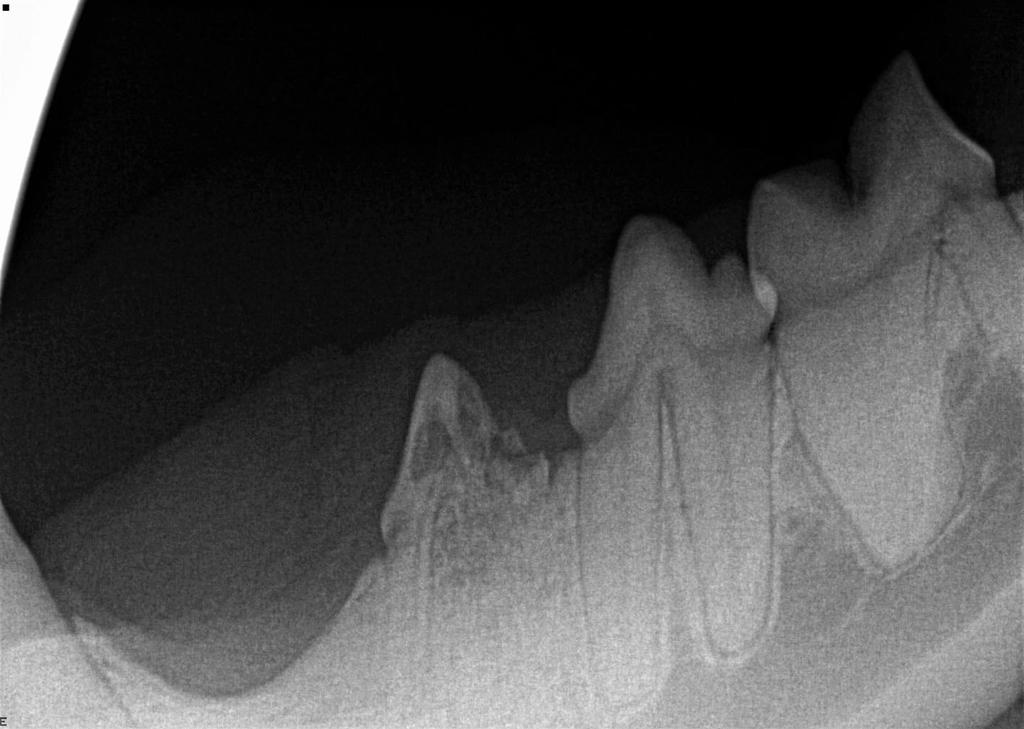

Dental X-Rays are especially important in feline dentistry. This is because cats very commonly get a disease called tooth resorption, where cells called odontoclasts destroy and dissolve the tooth, later replacing it with bone. This is a painful and irreversible disease and the only treatment is extraction of the affected teeth. Because the disease starts with the tooth root below the gumline and only starts affecting the visible crown of the tooth much later in the disease process, we cannot know which teeth are affected without taking radiographs.

Below shows an image of a normal tooth on dental X-Ray compared to a tooth that is undergoing tooth resorption in the three images below the main one.

Dental X-Rays can also be used in a number of other situations, including to assess for pulp necrosis, periodontal disease, jaw fractures and retained root fragments.